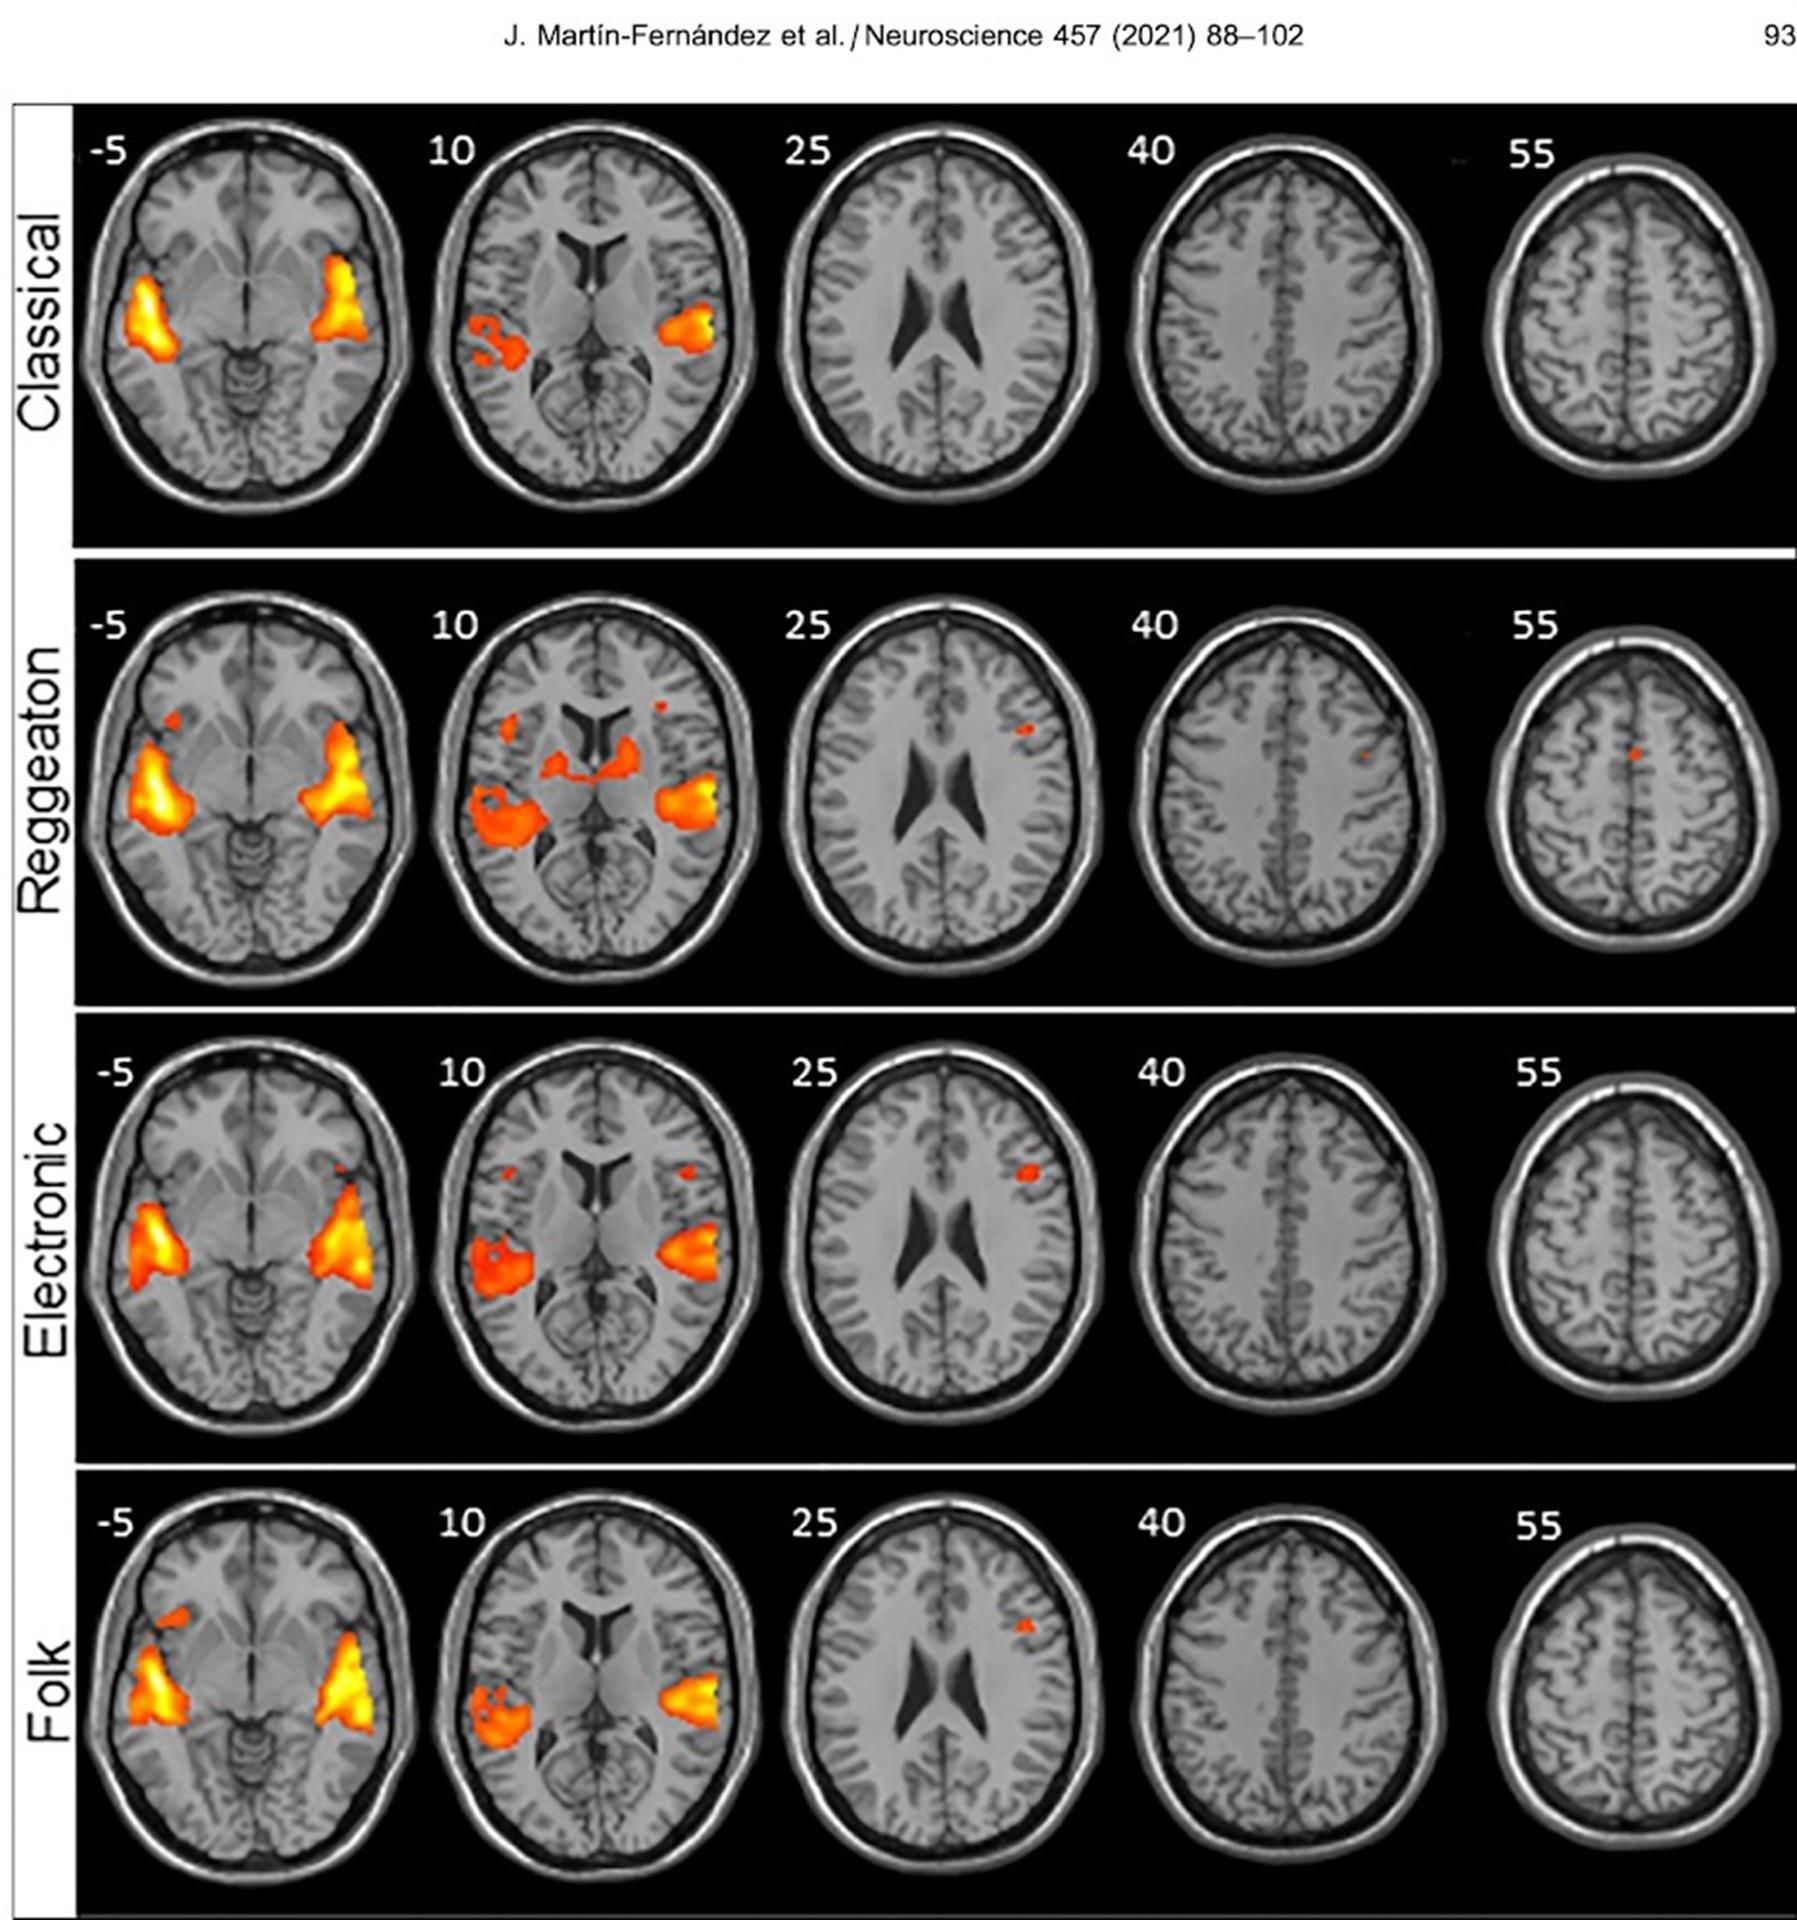

Frente a la música clásica, el folclor y la electrónica, el reguetón provoca una mayor activación en las regiones del cerebro encargadas de procesar no sólo los sonidos, sino también el movimiento, según un estudio llevado a cabo por investigadores canarios sobre la actividad cerebral que produce escuchar diferentes estilos musicales.

Los investigadores analizaron por un lado anatómicamente el cerebro de cada participante y luego la señal BOLD, que consiste en ver qué áreas del cerebro reclutan oxígeno (que es lo que sucede cuando se activan) y a través de un software se representaron con diferentes colores según se activasen más o menos.

Y fue el reguetón el que mostró mayor activación en las regiones del cerebro encargadas de procesar los sonidos (áreas auditivas) y de procesar el movimiento (áreas motoras), unas diferencias que resultaron mayores cuando se comparaban con la música clásica.

La electrónica también mostró una mayor activación de las regiones motoras, pero significativamente menor en comparación con el reguetón “y lo que más nos llamó la atención fue la activación de una región primitiva del cerebro: los ganglios basales”.

La mayor activación provocada por el reguetón implica que hay más regiones cerebrales auditivas y motoras que se activan y por lo tanto hay una mayor maquinaria trabajando en procesar la música.